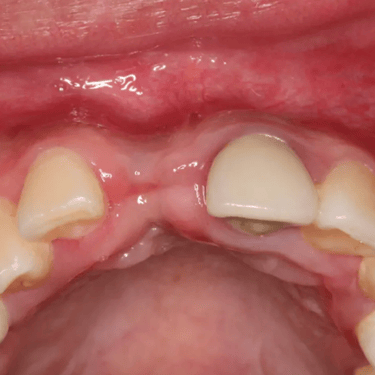

Pérdida de un diente único

La pérdida de un diente único es cuando un solo diente se ha caído o ha sido extraído, y se necesita un implante para reemplazarlo.

Los pacientes pueden notar un espacio donde solía estar el diente. Esta condición puede afectar la estética y la función masticatoria.

El tratamiento incluye la colocación de un implante dental para restaurar el diente perdido.